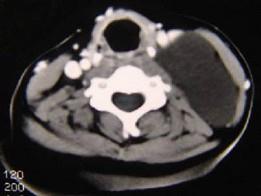

问题 男性,40岁,颈部出现无痛性囊性包块2年余,CT扫描如图所示,最可能诊断为()

选项 A.淋巴管瘤 B.血管瘤 C.淋巴结肿大 D.神经源性肿瘤 E.颈动脉鞘瘤

答案 A